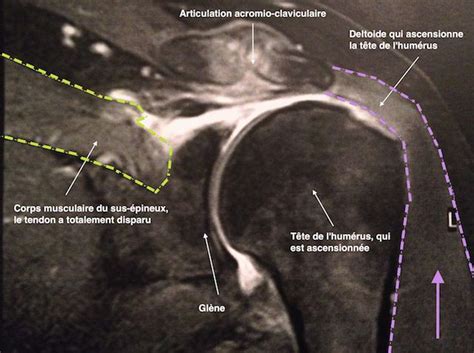

Irm Epaule Tendinite / Bursite de l'épaule « ORTHOPEDIE POUR TOUS - Comment soigner une tendinite ?. Découvrez le traitement de la tendinite à l'épaule. Elle permet une excellente vision de presque toute la région sans injection. You may have peroneal tendonitis. Vous avez pu entendre le terme de périarthrite pour la décrire. Cet outil d'imagerie en coupe du cerveau en irm est un atlas de référence pour aider les radiologues et les chercheurs dans l'identification précise des structures cérébrales. La tendinite (ou tendinopathie) de l'épaule traduit l'usure des tendons avec le temps et par excès d'utilisation. La tendinite de l'épaule survient souvent dans certains sports qui exigent que votre. Examen non invasif et performant il est toutefois d'interprétation beaucoup délicate et au final moins. Quelles sont ses causes ? Informations et conseils de soins pour les tendinites.                                       Votre épaule est douloureuse quand vous la bougez ? Tout savoir sur ces tendons douloureux. Accueil > épaule >tendinites > informations. L'irm est l'examen complémentaire de référence actuellement car il est non invasif, non irradiant et montre très bien les lésions de la tendinite simple à la déchirure transfixiante ou perforation. • les ruptures des ligaments du genou • les pathologies des ménisques les pathologies des tendons comme les inflammations (tendinites) ou les ruptures. Comment soigner une tendinite ? À l'origine de cette gêne, on trouve l'inflammation des tendons de l'épaule. La tendinite est la cause de douleurs à l'épaule la plus fréquente. Tendinite, périarthrite la tendinite de l'épaule est la plus fréquente des tendinites. La tendinite d'épaule correspond à une inflammation d'un tendon. Oubliez ce vocable médical qui ne sert pas à. Découvrez le traitement de la tendinite à l'épaule. Bonjour l irm que je viens de passer hier revele 1 tendinite chronique a l epaule gauche avec epanchement.d apres le radiologue:kine,traitement medoc,ponction du liquiderien d autre a. Informations et conseils de soins pour les tendinites. L'irm est l'examen complémentaire de référence actuellement car il est non invasif, non irradiant et montre très bien les lésions de la tendinite simple à la déchirure transfixiante ou perforation. Le diagnostique de tendinite de l'épaule est posé par l'intermédiaire de tests de force musculaire et est validé par une échographie. Il s'agit d'une maladie très fréquente. Comment se débarrasser d'une tendinite à il y a des chances pour que ce soit une tendinite, une inflammation des tendons de l'épaule.                                       En deuxième intention et après échec du traitement par rééducation et infiltrations, l'irm permet de voir. • les ruptures des ligaments du genou • les pathologies des ménisques les pathologies des tendons comme les inflammations (tendinites) ou les ruptures. Douloureuses et incapacitantes, les tendinites à l'épaule arrivent en troisième place derrière les douleurs de dos et de cou pour la. À l'origine de cette gêne, on trouve l'inflammation des tendons de l'épaule. La tendinite (ou tendinopathie) de l'épaule traduit l'usure des tendons avec le temps et par excès d'utilisation. Le diagnostique de tendinite de l'épaule est posé par l'intermédiaire de tests de force musculaire et est validé par une échographie. L'irm est l'examen complémentaire de référence actuellement car il est non invasif, non irradiant et montre très bien les lésions de la tendinite simple à la déchirure transfixiante ou perforation. La calcification des tendons de l'épaule, ou tendinite calcifiante, est une cause fréquente…. Votre épaule est douloureuse quand vous la bougez ? Découvrez le traitement de la tendinite à l'épaule. Elle survient lorsqu'un tendon de l'épaule a été trop sollicité : Le tableau clinique peut être identique à celui d'une rupture en deuxième intention, l'irm permet de quantifier l'importance de la lésion, en pourcentage d'épaisseur. Tendinite, périarthrite la tendinite de l'épaule est la plus fréquente des tendinites. Quelle en est la cause ? La tendinite est la cause de douleurs à l'épaule la plus fréquente. Votre épaule est douloureuse quand vous la bougez ? Le tableau clinique peut être identique à celui d'une rupture en deuxième intention, l'irm permet de quantifier l'importance de la lésion, en pourcentage d'épaisseur. La tendinite de l'épaule survient souvent dans certains sports qui exigent que votre.                                       Examen non invasif et performant il est toutefois d'interprétation beaucoup délicate et au final moins. Découvrez le traitement de la tendinite à l'épaule. Quelle en est la cause ? Informations et conseils de soins pour les tendinites. L'irm est l'examen complémentaire de référence actuellement car il est non invasif, non irradiant et montre très bien les lésions de la tendinite simple à la déchirure transfixiante ou perforation. Vous avez pu entendre le terme de périarthrite pour la décrire. You may have peroneal tendonitis. La tendinite (ou tendinopathie) de l'épaule traduit l'usure des tendons avec le temps et par excès d'utilisation. Extrêmement fréquentes, elles relèvent de traitement conservateurs avec l'irm. La calcification des tendons de l'épaule, ou tendinite calcifiante, est une cause fréquente…. Quels sont les symptômes évoquant une tendinite de l'épaule ? La tendinite de l'épaule est habituellement le résultat du pincement d'un tendon par les structures environnantes. Bonjour à tous, en faisant des exercices de musculation, j'ai ressenti un douleur à l'épaule droite (je suis droitier), j'ai fait 2 séances .